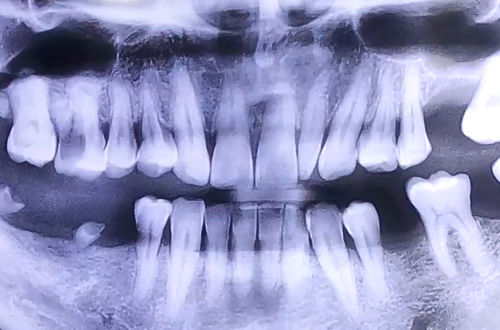

양쪽 모두 어금니 상태가 좋지 못하여 음식을 제대로 드시지 못하는 상태의 환자분 진료 내용입니다.

진료일지를 통해서 그 일례를 살펴봐 주시기 바랍니다.